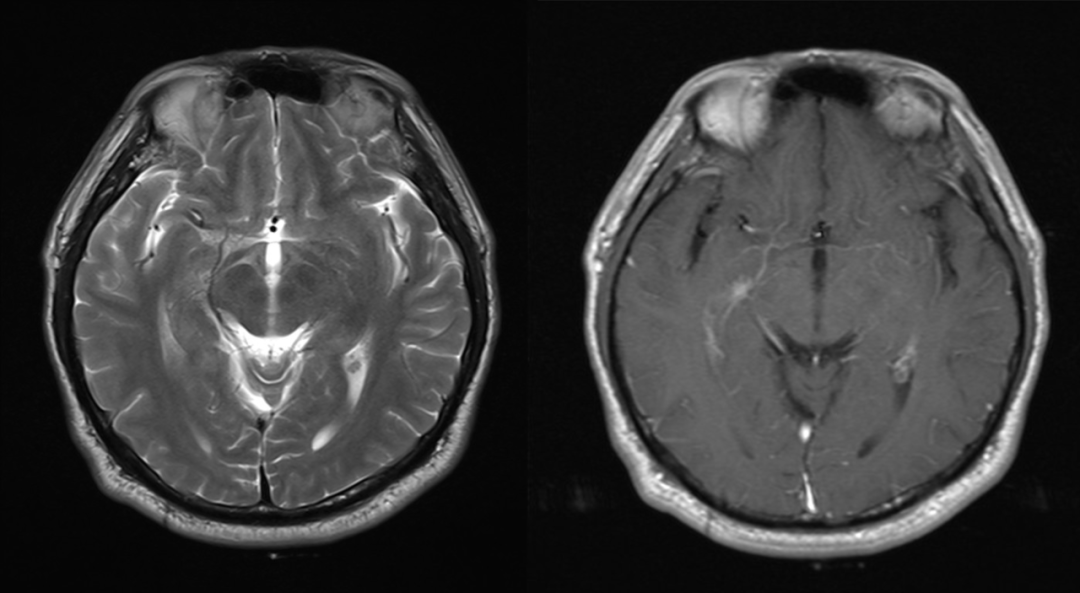

首次检查 2021-1-5 日发现左侧颞叶强化结节,轴矢冠状位都能看到,但是平扫看不到,周围亦未见水肿信号,此时没经验的诊断医生估计会考虑为转移瘤,一直困扰着患者和临床医生。但是在其余 7 次检查中 2021-3-2 至 2022-6-22 一年半多的时间,左侧颞叶强化结节仍然存在,并且基本没啥变化,如果是转移瘤会这么长时间无任何干预都处于一个静止状态吗?,此时是不是需要考虑其他的诊断?,究竟是什么呢,有经验的医生肯定会想到:是毛细血管扩张症。

仔细观察本例左侧颞叶强化结节,中心为明显强化,周围为稍淡淡样的强化,此为毛细血管扩张症的特点。